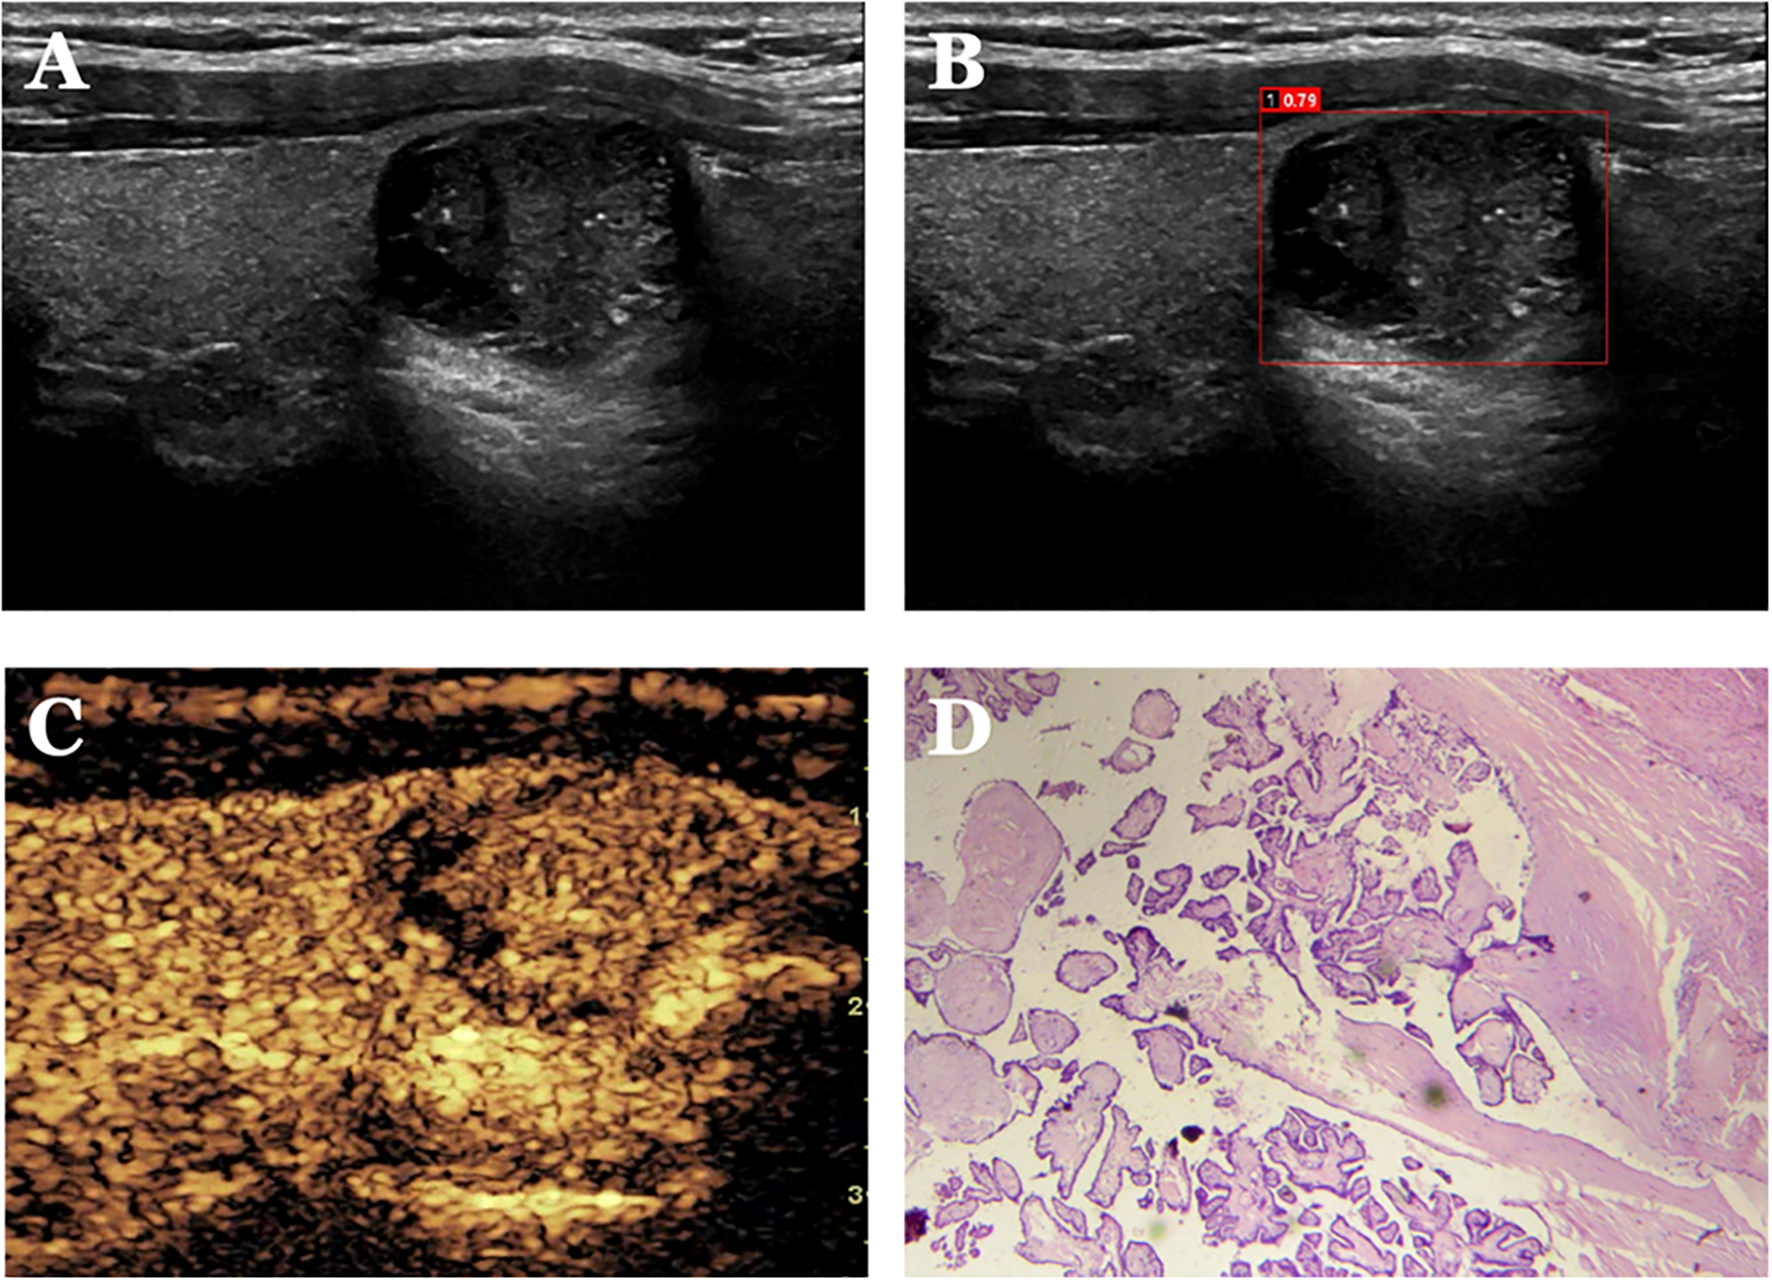

Figure 5

Panel A shows an ultrasound image of a suspicious lesion. Panel B highlights the lesion with a red box and numerical annotation. Panel C displays an enhanced ultrasound image with a different texture. Panel D presents a histological slide with pink and purple stained tissue sections.

Figure 5. Case 1. The patient is a 34-year-old male. (A) shows a cystic solid nodule in the lower pole of the right lobe of the thyroid gland; (B) shows a probability value of 0.79 quantified by AI software for benign and malignant, suggesting malignancy; (C) shows isoenhancement of the solid part of the nodule by CEUS (identifying dotted strong echogenicity as microcalcifications) with indistinct borders and an incomplete peripheral ring of enhancement, with a CEUS score of 4; (D) shows pathological findings of papillary thyroid carcinoma (HE, ×200).